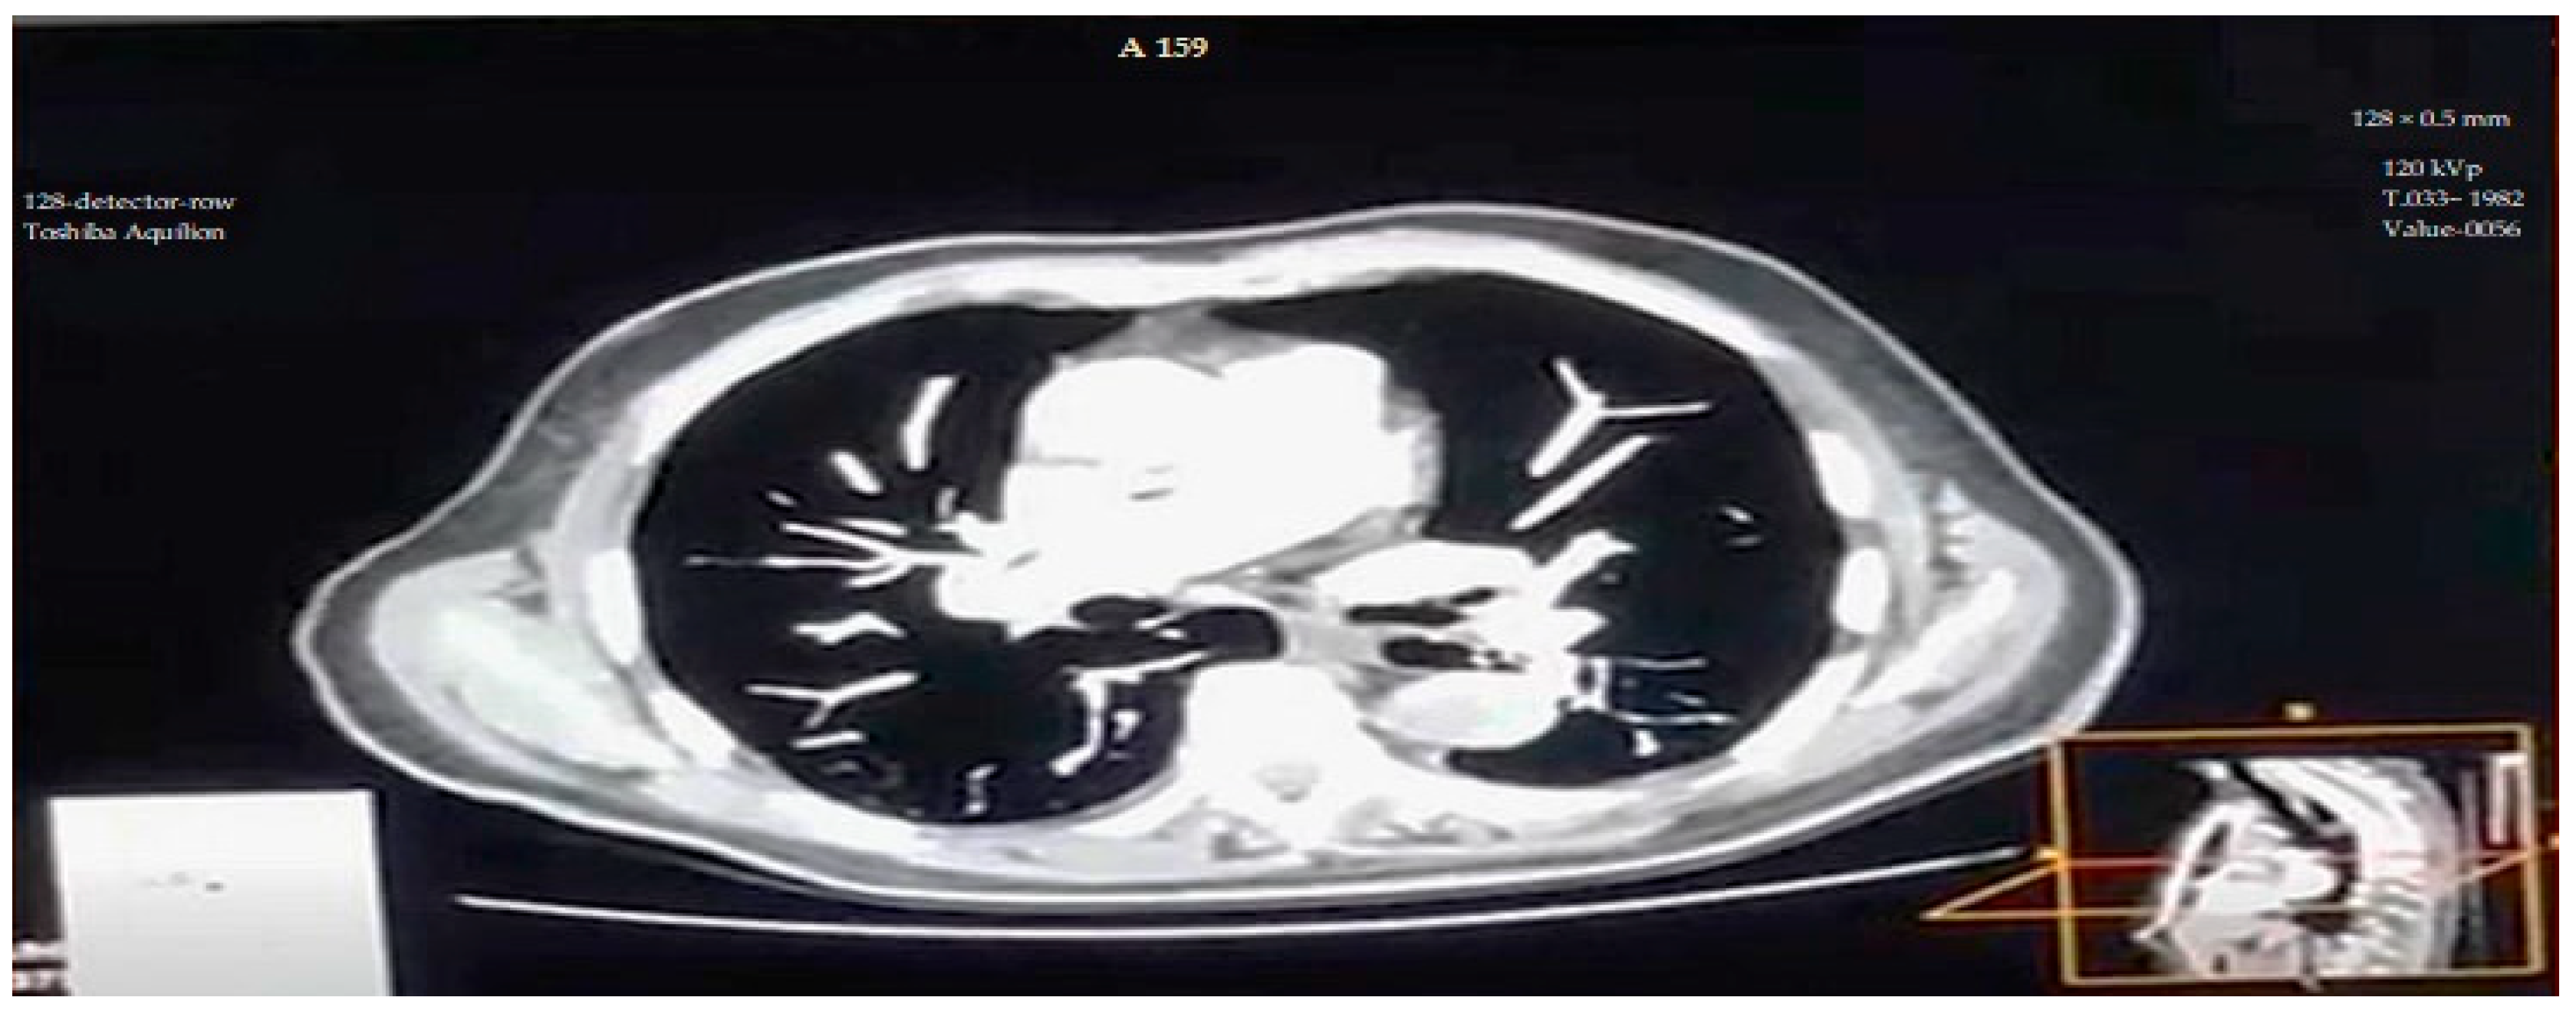

4.6. Visual Findings and Clinical Implications